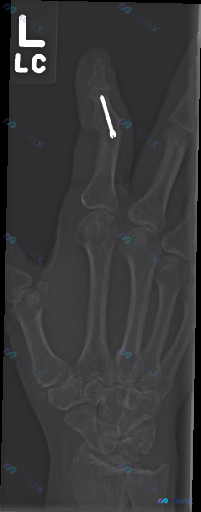

整理到一份左手斜位X光片的影像资料,先不结合额外病史,只看影像本身: 核心影像表现: 1. 左手示指中节指骨骨干内可见一枚金属钉状内固定物,跨越区域有骨痂形成(骨密度增高、形态改变) 2. 其余可见腕骨、掌骨、指骨骨皮质连续,未见明确急性骨折/脱位 3. 可见关节间隙尚可,无明显严重骨侵蚀或退变 4...